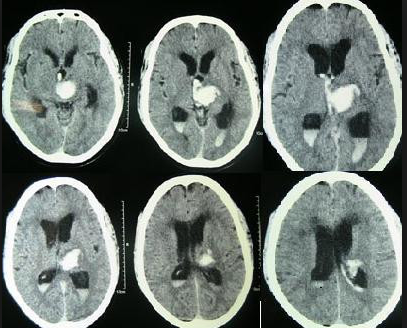

Case Scenario: A 54 year old man presents with acute onset of headache. His blood pressure 210/110mmHg. CT scan shows and acute bleed.

Question: Does rapid lowering of blood pressure improve outcomes in patients with acute intracerebral hemorrhage?

Acute spontaneous intracerebral hemorrhage is a bad thing to have happen. Bleeding in the brain is not good. Patients often do poorly and their outcome has been associated with their blood pressure. The blood pressure often elevates to very high numbers. Current AHA/ASA Guidelines from 2010 recommend lowering BP as follows: